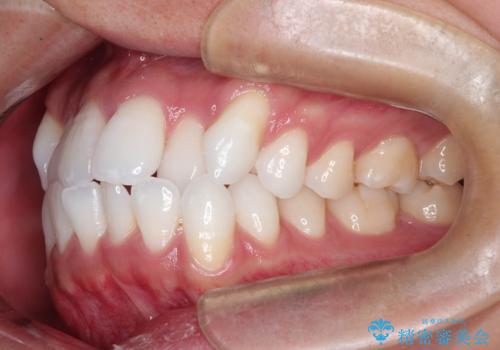

- 前歯のガタつき(叢生)を主訴にご来院されました。精密検査の結果、歯を並べるためのスペースが著しく不足していることが判明しました。

非抜歯で無理に並べようとすると、歯列が外側に広がり、前歯が前方に突き出て口元が突出してしまうリスクがありました。患者様の「これ以上前歯を外に出したくない」という強いご希望を重視し、上下左右の4番目の歯(第一小臼歯)を計4本抜歯してスペースを確保する計画を立案。装置は、装置の見た目を考慮し、白く目立ちにくい審美ワイヤーを選択しました。